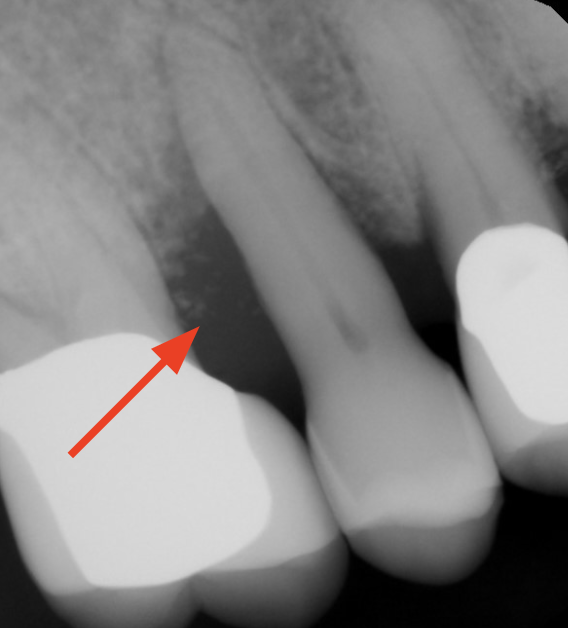

Gum Grafting